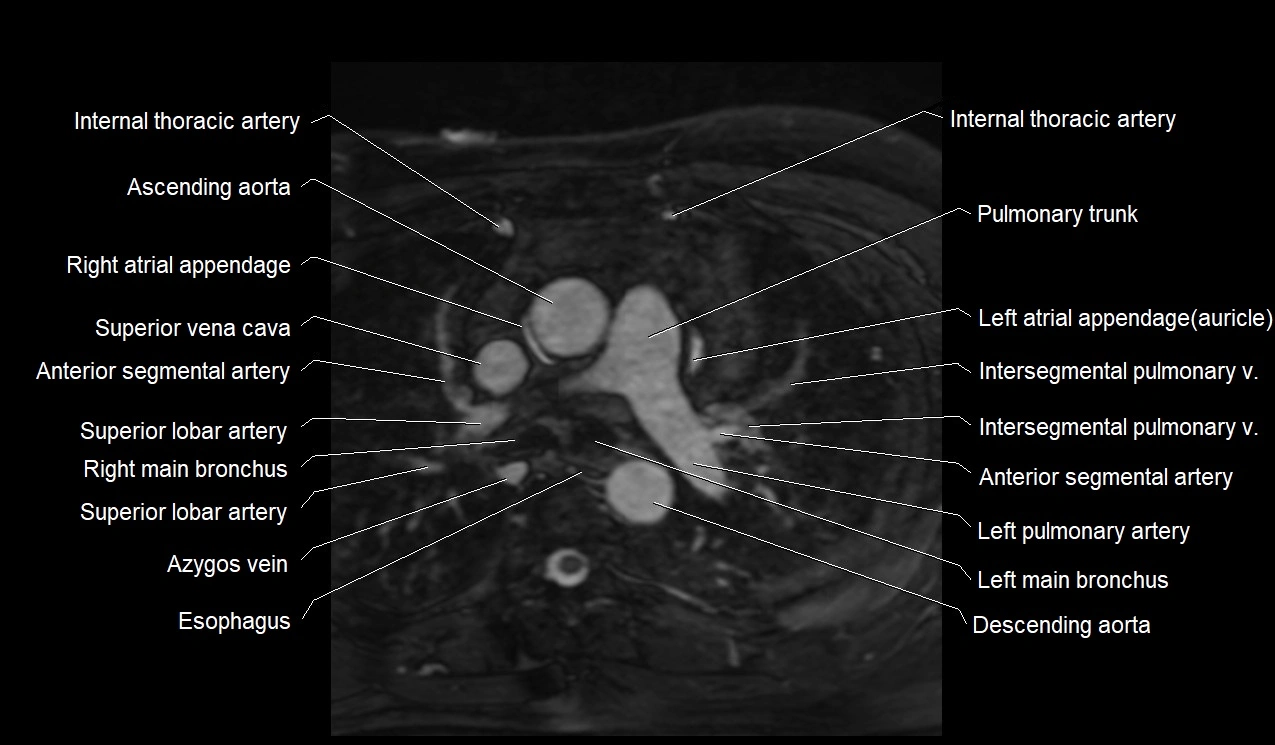

CT images